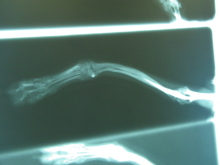

これはヨソから持ってきた画像なので

ここまでひどくはないんだけど

前足の骨が湾曲してるっつーの?

それにより、ヒジと手首の関節がまっすぐにつながってねーそうで。